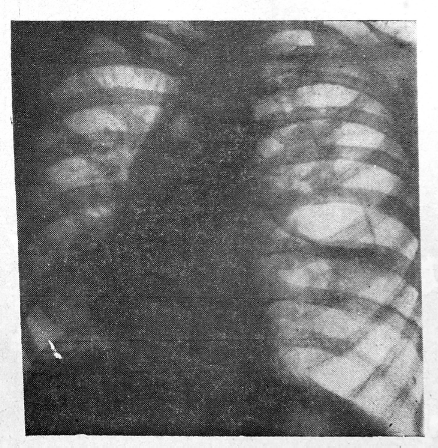

У Ш., 59 лет, при обычном рентгеновском исследовании отмечена зубчатость большой кривизны. Пальпаторно признаков нарушения эластичности выявить не удалось, и зубчатость была объяснена петлистостью утолщенных складок слизистой (рис. 1, см. вклейку). Однако у рентгенолога в оценке состояния большой кривизны возникли сомнения. Было решено вызвать больную для повторного просвечивания. В результате исследования, проведенного двуконтрастным методом, там, где обратила на себя внимание зубчатость большой кривизны, рисунок рельефа остался стабильным, в то время как во всех других отделах складки сгладились. Между обрывами плавных очертаний большой кривизны стенка желудка оказалась деформированной, ригидной (рис. 2). Заключение: раковая опухоль желудка. Больная госпитализирована. При гастроскопии на передней стенке и на большой кривизне желудка в нижней трети его тела выявлена плоская опухоль с четко очерченным валикообразным бугристым краем и изъязвлением в центре (рис. 3). При пробной лапаротомии найдена раковая опухоль 4X10 см, располагающаяся в области тела желудка. Имеются метастазы.

Рис. 3. Гастрограмма той же больной. На передней стенке и на большой кривизне желудка в нижней трети его тела определяется плоская опухоль с четко очерченным валикообразным бугристым краем и изъязвлением в центре.